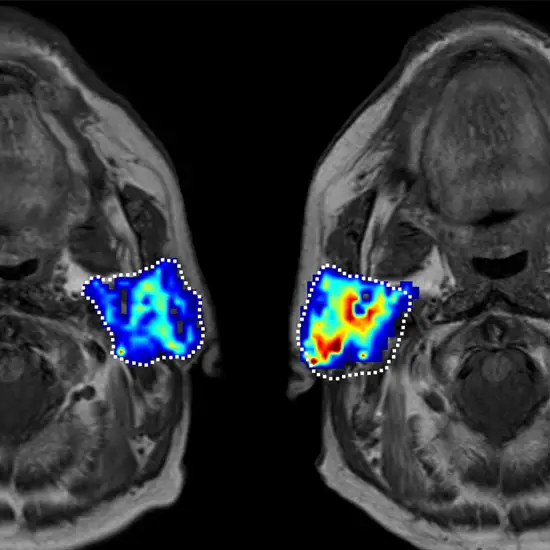

Utilizing a contrast agent, the magnetic resonance imaging (MR) technique known as the parotid gland generates images of superior quality of the salivary gland.

This examination is used to assess the parotid gland's mass, which reveals the tumor's extent, its contour, signal features, and the connection between the tumour and the facial nerve.